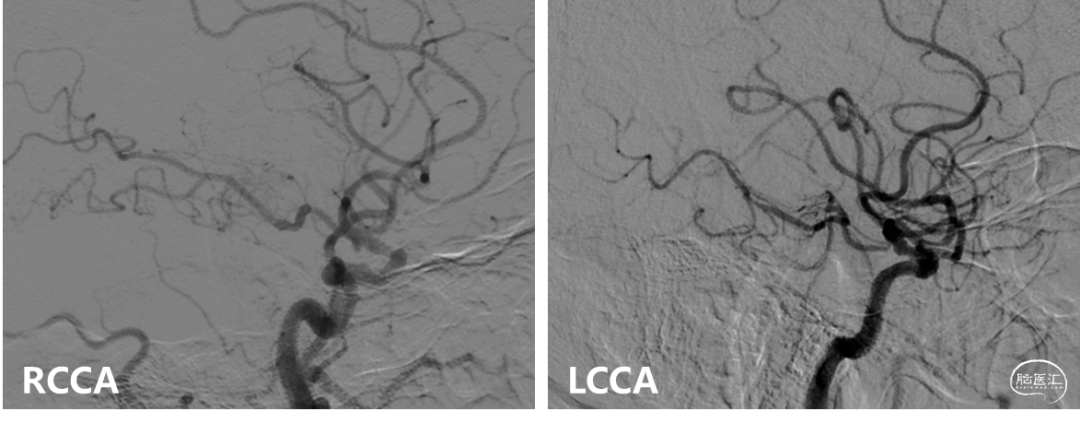

左右滑动切换图片

基底动脉中下段重度狭窄,串联病变;右椎动脉纤细,止于右侧小脑后下动脉。椎动脉造影双侧大脑后动脉未见显影,颈动脉造影可见双侧后交通动脉开放。

中间导管送至左侧椎动脉V2段远端,造影双侧大脑后动脉仍未见显影。